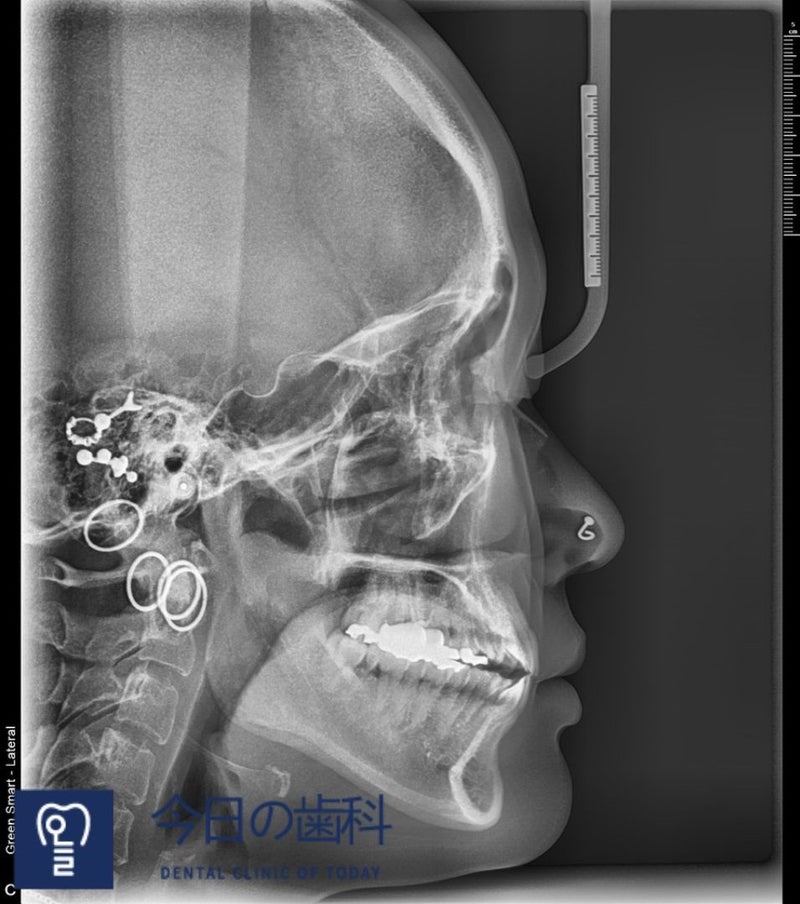

精密診断のために写真も何枚か撮りましたが

見れば見るほど矯正を始めてよかったと感じる..(笑)

横から見るととても見ものだ···

チェックされたところだけ刺されるのだった~~~!~!~!!

実はご飯を食べる時

前歯と奥歯の内側だけを噛んで食べたもの..ふぅ

その間に位置した歯たちが今まで遊んでいた..

僕の横顔···

あごがどうしてこんなに厚いのか..^^